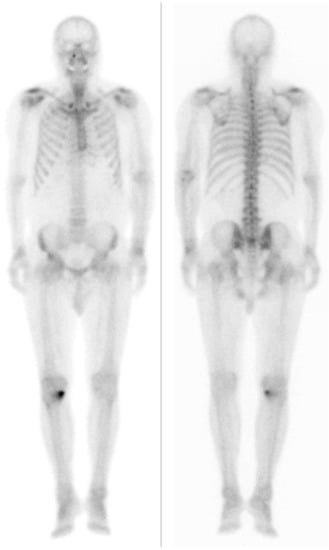

Visualization of Dialysis-Related Amyloid Arthropathy on 18F-FDG PET-CT Scan

Cheon, M.; Yoo, J. Visualization of Dialysis-Related Amyloid Arthropathy on 18F-FDG PET-CT Scan. Diagnostics 2022, 12, 113. https://doi.org/10.3390/diagnostics12010113